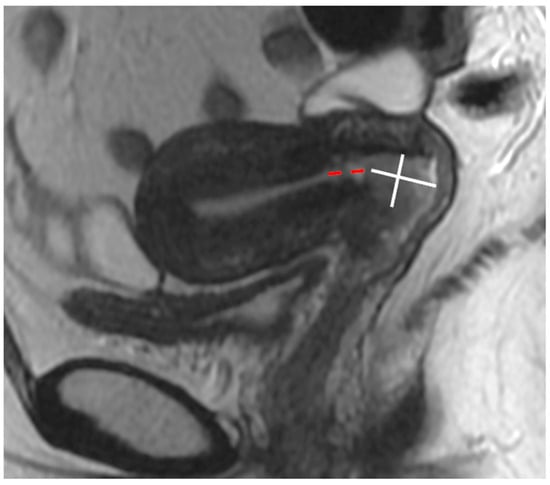

| Small FOV Sagittal T2WI | Accurate tumour size, local staging (e.g., vaginal, bladder, rectal invasion) |

| Small FOV Axial oblique T2WI | Local staging, parametrial and pelvic sidewall involvement |

| Sagittal and axial oblique DWI and ADC maps (corresponding to sagittal and axial oblique T2WI) | Identifying small isointense tumours, unsuspected bone metastases |